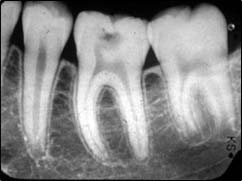

RÉTROALVÉOLAIRE :

Il s’agit de radios de petites tailles placées et orientées dans votre bouche et ciblant un secteur de une à trois dents. Elles permettent une vision plus précise de certains détails.